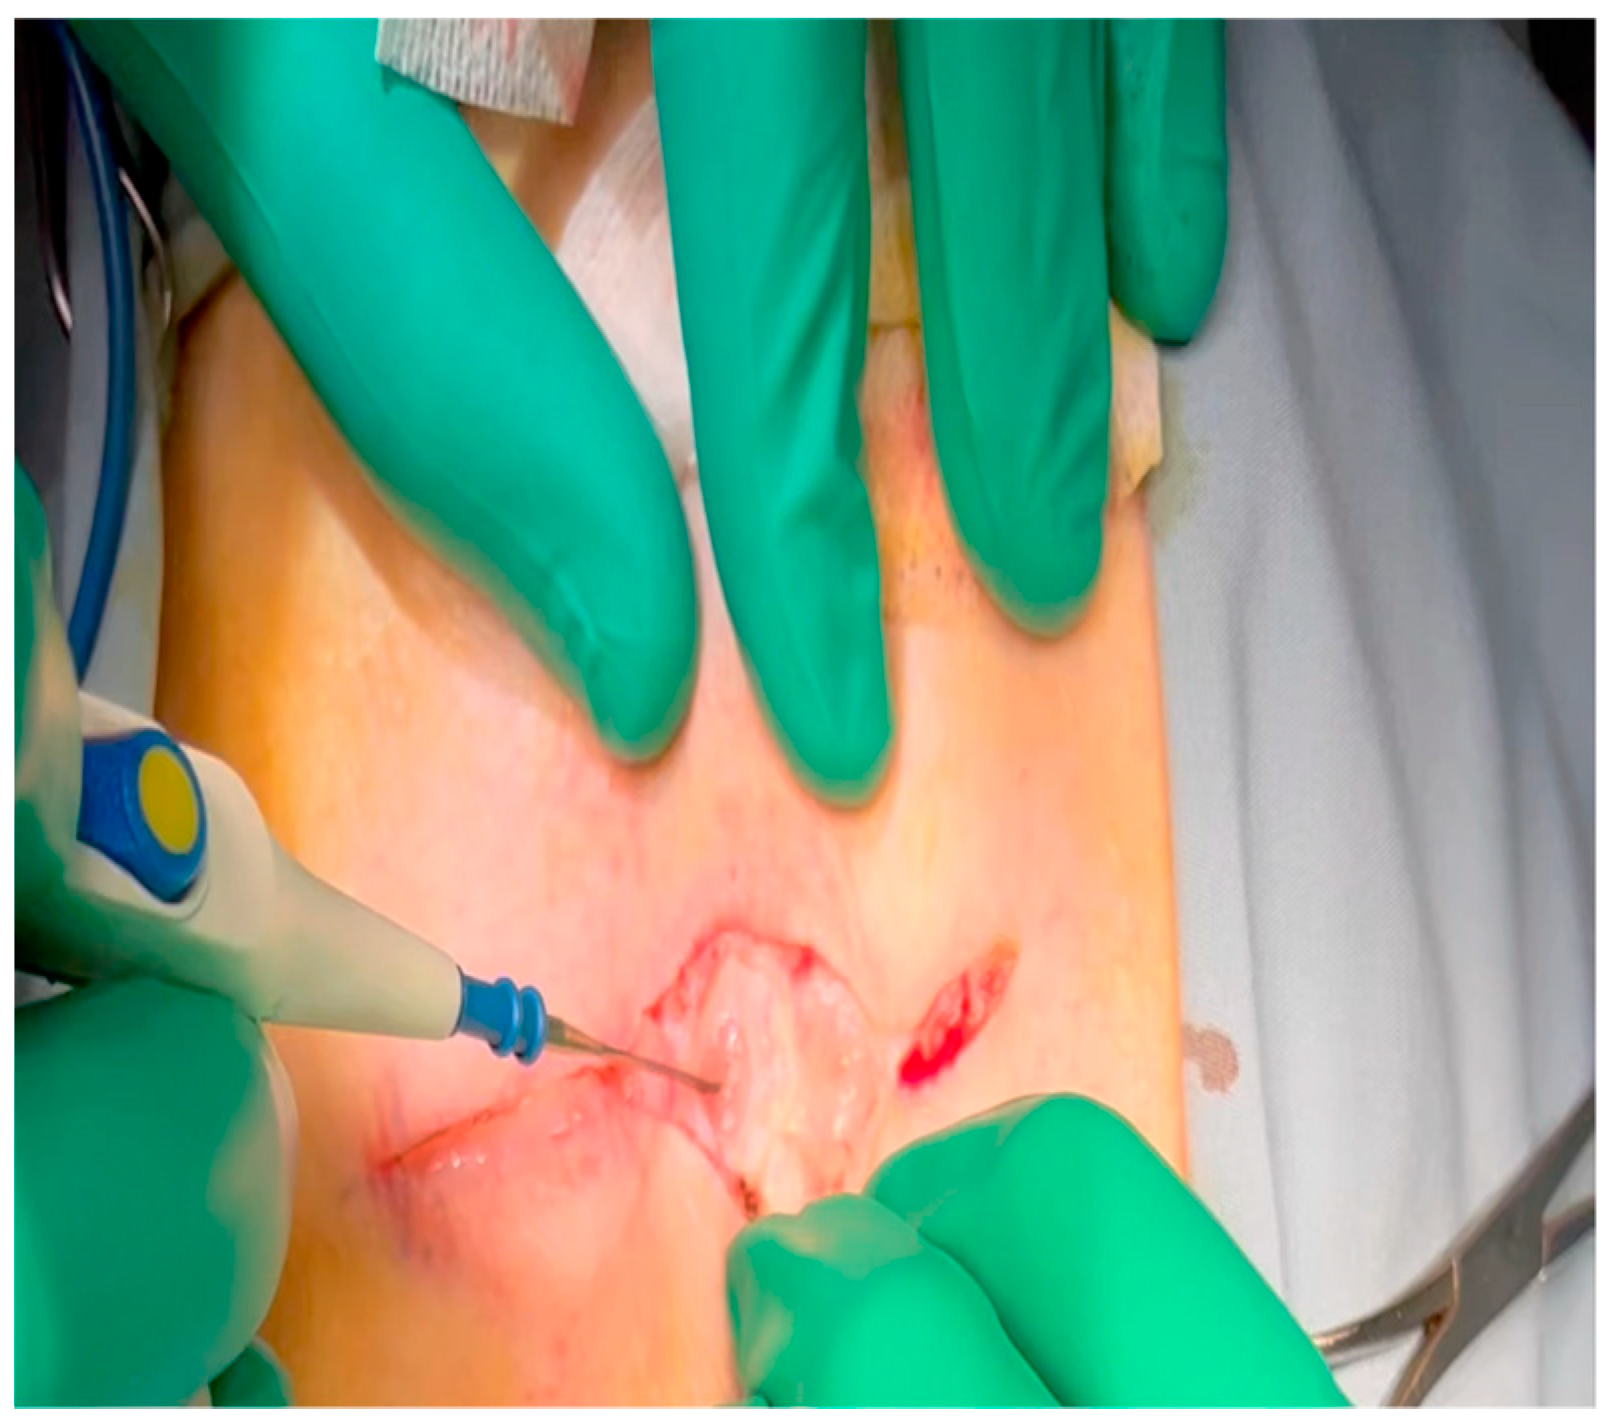

- Femoral arterial catheterization: after intubation and induction of general anesthesia, lidocaine is injected as above for the thoracotomy, but in this case, within the left or right inguinal crease, according to surgeon preference.

- A combination of sharp and blunt dissection using electrocautery and a right-angle clamp is utilized to expose the femoral artery, which will thus be cleared of surrounding tissue and encircled with vessel loops.

- Once the animal is heparinized (see below: the timing of this depends on progress made in the concurrently performed sternotomy by a co-surgeon), the Seldinger technique is used to obtain arterial access: an 18-gauge needle punctures the artery; a fine intravascular wire is placed through the needle; the needle is removed over the wire; and an appropriately sized dilator and sheath are advanced together over the wire to establish durable arterial access.